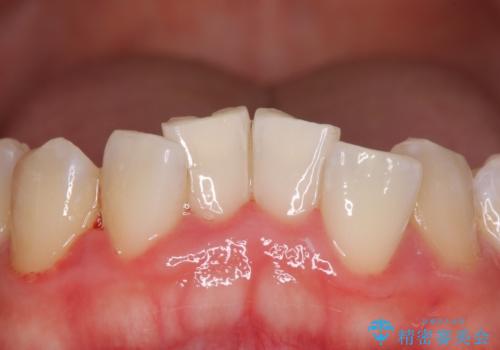

- 右上前歯2本を被せ物にする予定があるため、被せ物の治療前にホワイトニングをご希望されました。

下の前歯に着色(ステイン)が見られたため、処置前クリーニングを行い、着色を除去しました。ホワイトニング後は全体的に白くなりました。ご希望の被せ物の色味になるまでは再度オフィスホワイトニングまたは、ホームホワイトニングの併用をおすすめしました。